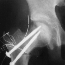

- Two large pins are inserted parallel into proximal and distal

fragments, and femoral head is rotated anteriorly by handling

proximal pin.

- After adequate rotation, a large screw is inserted in valgus

position. An A-P X-ray should be taken to ensure the weight-bearing

portion is well apposed and the neck-shaft angle. Then a Steinman

pin is removed and another large pin is inserted. The A-O compression

screw is ineffective because of its thin shank.